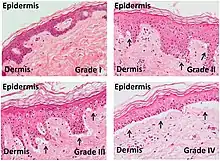

Psoriaform dermatitis

Examining multiple deeper levels is recommended if initial cuts do not correlate well with the clinical history.[2]

Psoriaform dermatitis typically displays:[2]

- Regular epidermal hyperplasia, elongation of the rete ridges, hyperkeratosis, and parakeratosis.

- Usually:A superficial perivascular inflammatory infiltrate

- Often: Thinning of epidermal cells overlying the tips of dermal papillae (suprapapillary plates), and dilated, tortuous blood vessels within these papillae

Further histopathologic diagnosis is performed by the following parameters: